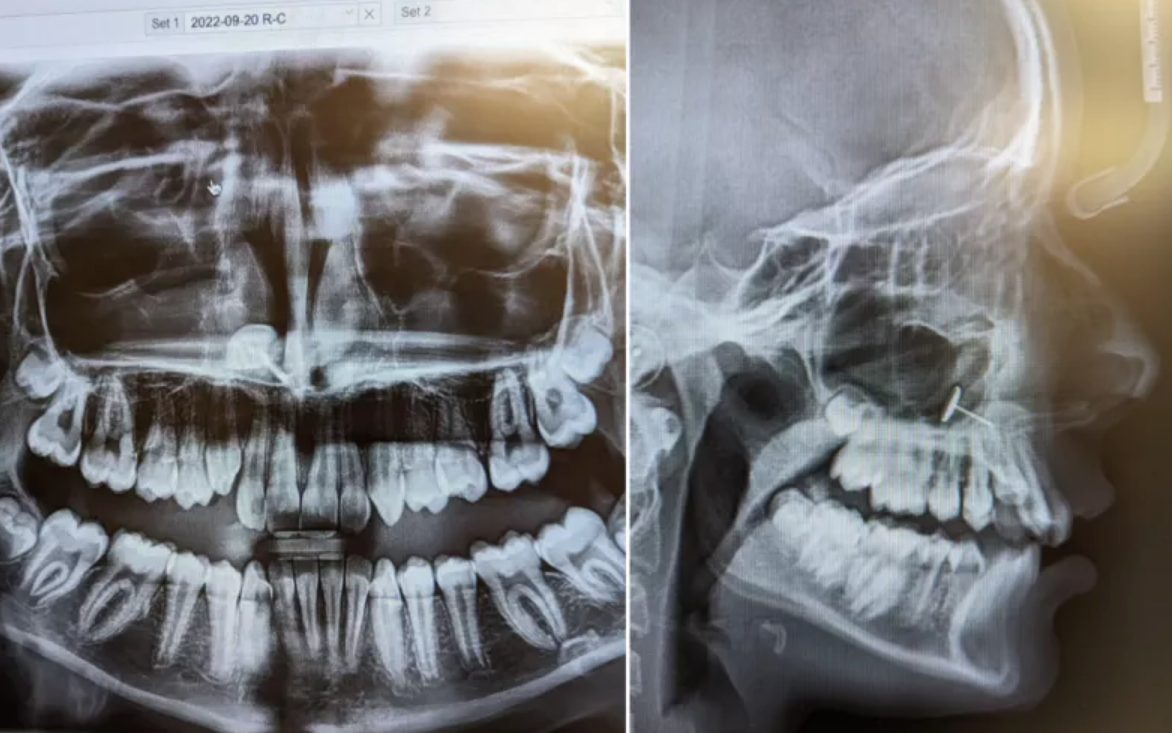

«Ο ορθοδοντικός επέστρεψε στο δωμάτιο και έβαλε τις ακτινογραφίες στην οθόνη», είπε η Οφέλια στο Newsweek. «Τις είδαμε όλοι ταυτόχρονα και πέρασαν αρκετά λεπτά προσπαθώντας να καταλάβουμε τι βλέπαμε».

- Αυτό, που έβλεπαν, φαινόταν να είναι ένα μικρό κομμάτι μετάλλου, που είχε σφηνωθεί στα ιγμόρεια της μύτης της κόρης της. Η Οφέλια δεν είχε ιδέα πώς βρέθηκε εκεί, αλλά η κόρη της ήξερε ακριβώς τι είχε συμβεί.

Όλα αυτά μέχρι την επίμαχη επίσκεψη στον ορθοδοντικό και την ακτινογραφία που

αποκάλυψε τα πάντα. Η Οφέλια δημοσίευσε τις εικόνες των ακτινογραφιών στον

λογαριασμό της στο Reddit, που έγιναν αμέσως viral. Τα καλά νέα είναι ότι η ιστορία είχε αίσιο τέλος. «Μόλις καταλάβαμε τι ήταν και πώς βρέθηκε εκεί, τηλεφώνησα στον ΩΡΛ που της είχε αφαιρέσει τις αμυγδαλές πριν μερικά χρόνια, και εκείνος το αφαίρεσε με μία πολύ μακριά ιατρική λαβίδα», είπε η Οφέλια.